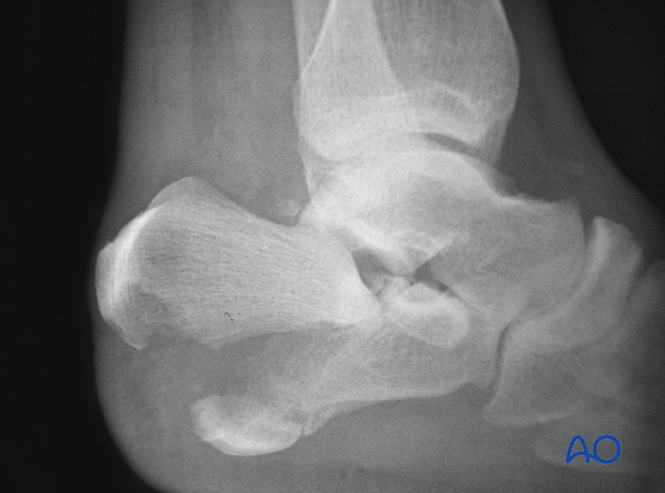

X线投照体位

踝关节侧位片可显示跟骨后结节显著移位,并明确骨折是否累及距下关节(subtalar joint)或完全位于关节外。

贝氏角(Böhler’s angle)

侧位X线测量贝氏角减小提示关节损伤及塌陷程度。正常值为25-40度,若角度>15度可考虑保守治疗。